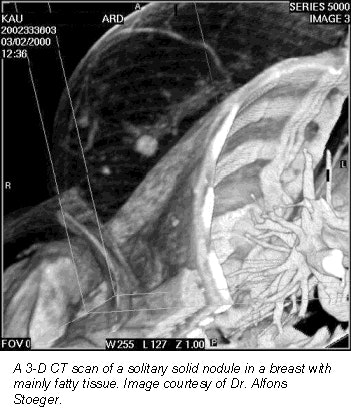

According to the results, breast CT found solitary solid nodules (>1.5 cm) in four patients. Single or multiple cysts (>5 mm) were found in eight patients, and macrocalcifications (>3 mm) were found in six women. Breast CT could not discern microcalcifications, which had been previously identified with mammograms, because of limited spatial resolution, Stoeger said.

The group concluded that CT was not useful for detecting microcalcifications, but that the modality may have potential for preoperative planning.

"We think that there may be a potential for this method in preoperative planning of breast disease (including the axilla) in the follow-up of certain benign masses, or even in planning radiotherapy after breast surgery," Stoeger said. "This does not mean that a CT scan should be performed for these reasons. But if these patients get a scan for other reasons, and the data exists, it could be post-processed and used for these issues instead of other time-consuming and expensive exams."